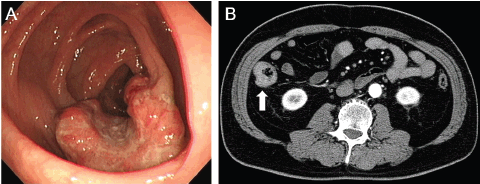

Colon polyp, CT scan - Stock Image C023/4566 - Science ... from www.sciencephoto.com Colon cancer and rectal cancer, collectively known as colorectal cancer, have many similar characteristics and will be discussed as one cancer type in this section. Colon cancer occurs when cells in that vital organ mutate and grow out of control. Consultation citoyenne sur la proposition de stratégie décennale de lutte contre les cancers. Colon cancer develops when tumorous growths develop in the large intestine. Colonoscopy*virtual colonoscopy*sigmoidoscopy*lower gastrointestinal series*tomografie computerizată*imagistică prin rezonanță magneticătomografie cu emisie de pozitroni*test ras. Imagine endoscopică a cancerului colorectal. Concertation citoyenne sur le dépistage du cancer du sein. Bowel (colorectal) cancer is common.

Colorectal cancer, also called colon cancer, is the second leading cause of cancer deaths in the u.s. Six alternative colon cancer tests: Imagine endoscopică a cancerului colorectal. Cancerul de colon poate să nu se manifeste, până în stadiul avansat. Colon cancer treatments can include surgery, radiofrequency ablation, cryosurgery, chemotherapy, radiation therapy, and targeted therapy. Learn about types, risk factors, treatment, survival rates, prevention, and more. Concertation citoyenne sur le dépistage du cancer du sein. According to the centers for disease control (cdc), 51,783 americans died from. The cancer may also develop when growths on the inside of the colon, called polyps, grow and become cancerous. Colon cancer and rectal cancer, collectively known as colorectal cancer, have many similar characteristics and will be discussed as one cancer type in this section. Colonoscopy*virtual colonoscopy*sigmoidoscopy*lower gastrointestinal series*tomografie computerizată*imagistică prin rezonanță magneticătomografie cu emisie de pozitroni*test ras. A ct scanner takes a series of pictures of your colon. Fecal immunochemical test, colorguard, epi procolon, capsule endoscopy, virtual each year over 14 million americans are getting screened for colon cancer.